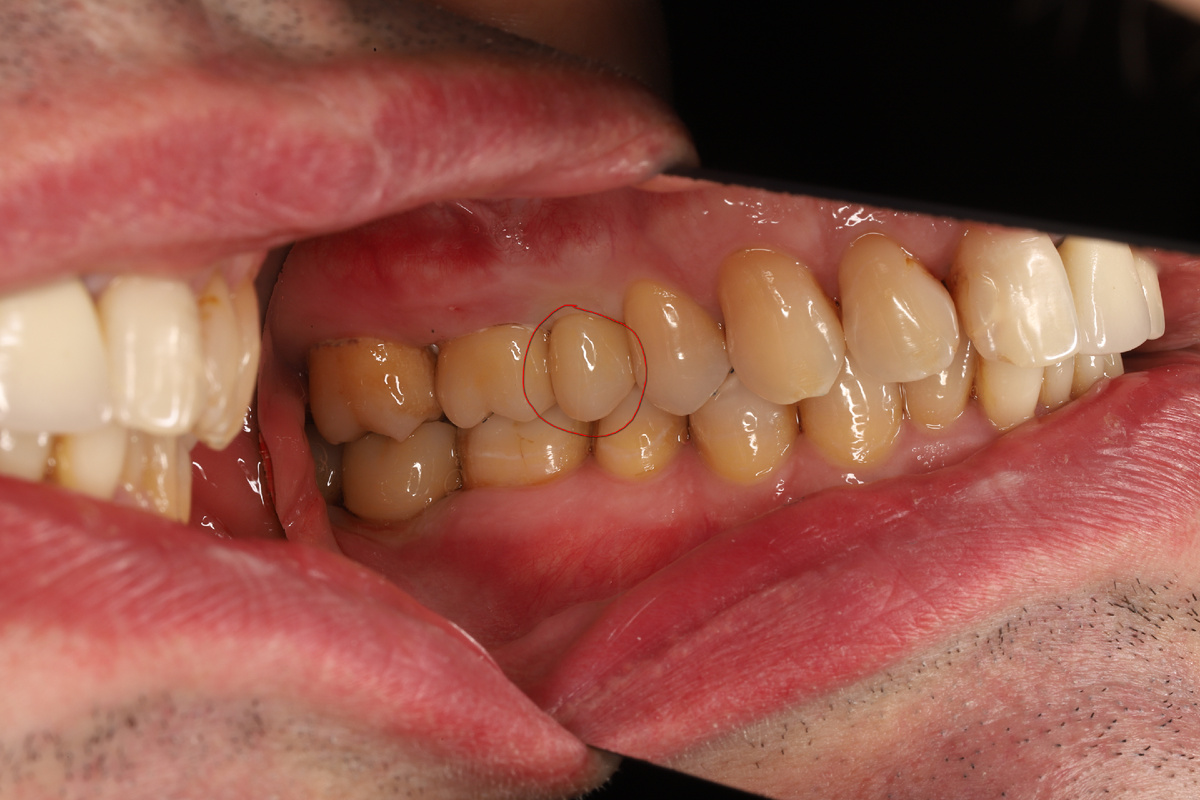

Так выглядит мостовидный протез, установленный на обточенные зубы. Фото взято из сети интернет.